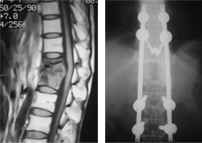

결핵성척추염

결핵성척추염 수술 전/후 X-ray

수술 전

수술 후